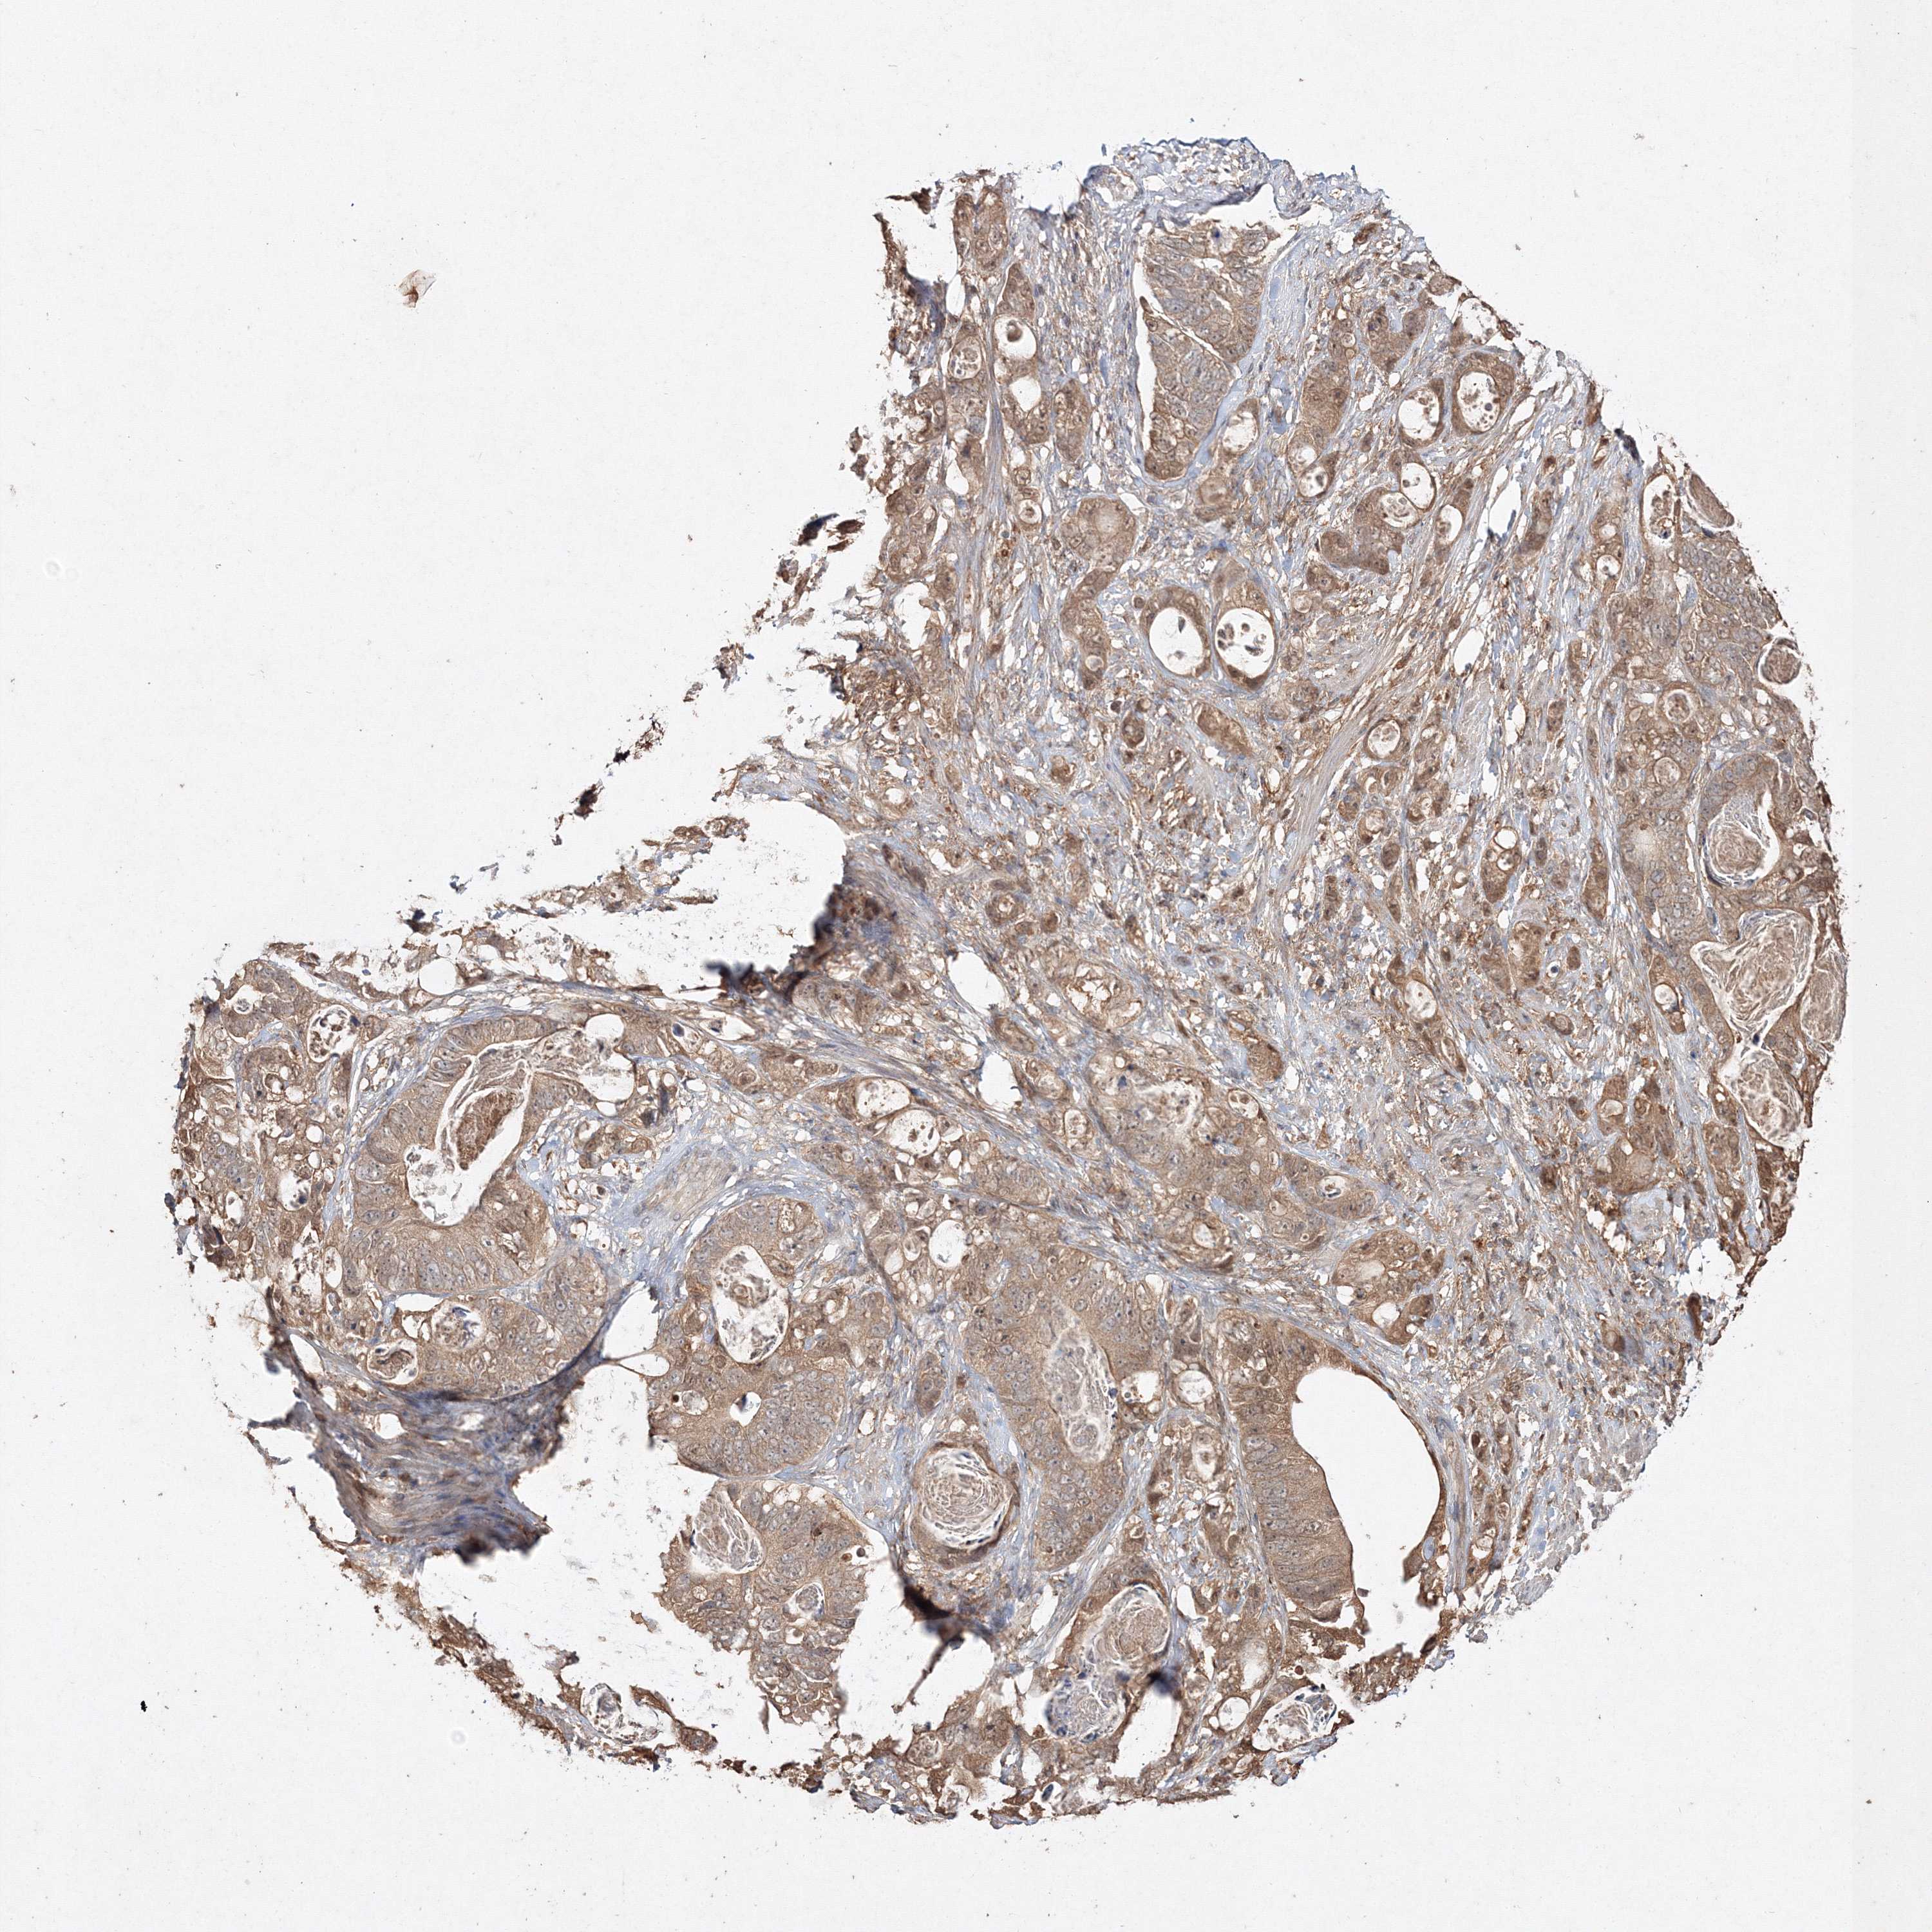

STOMACH CANCER - Protein expressioni

A mouse-over function shows sample information and annotation data. Click on an image to view it in a full screen mode. Samples can be filtered based on level of antibody staining by selecting one or several of the following categories: high, medium, low and not detected. The assay and annotation is described here.

Note that samples used for immunohistochemistry by the Human Protein Atlas do not correspond to samples in the TCGA dataset.

Antibody stainingi

Antibody staining in the annotated cell types in the current human tissue is reported as not detected, low, medium, or high, based on conventional immunohistochemistry profiling in selected tissues. This score is based on the combination of the staining intensity and fraction of stained cells.

Each image is clickable and will lead to virtual microscopy that enables deeper exploration of all samples and also displays staining intensity scores, fraction scores and subcellular localization as well as patient and tissue information for each sample.

Antibody HPA042745

Antibody CAB034320

Staining

High

Medium

Low

Not detected

Intensity

Strong

Moderate

Weak

Negative

Quantity

>75%

75%-25%

<25%

None

Location

Nuclear

Cytoplasmic/membranous

Cytoplasmic/membranous,nuclear

Adenocarcinoma, NOS